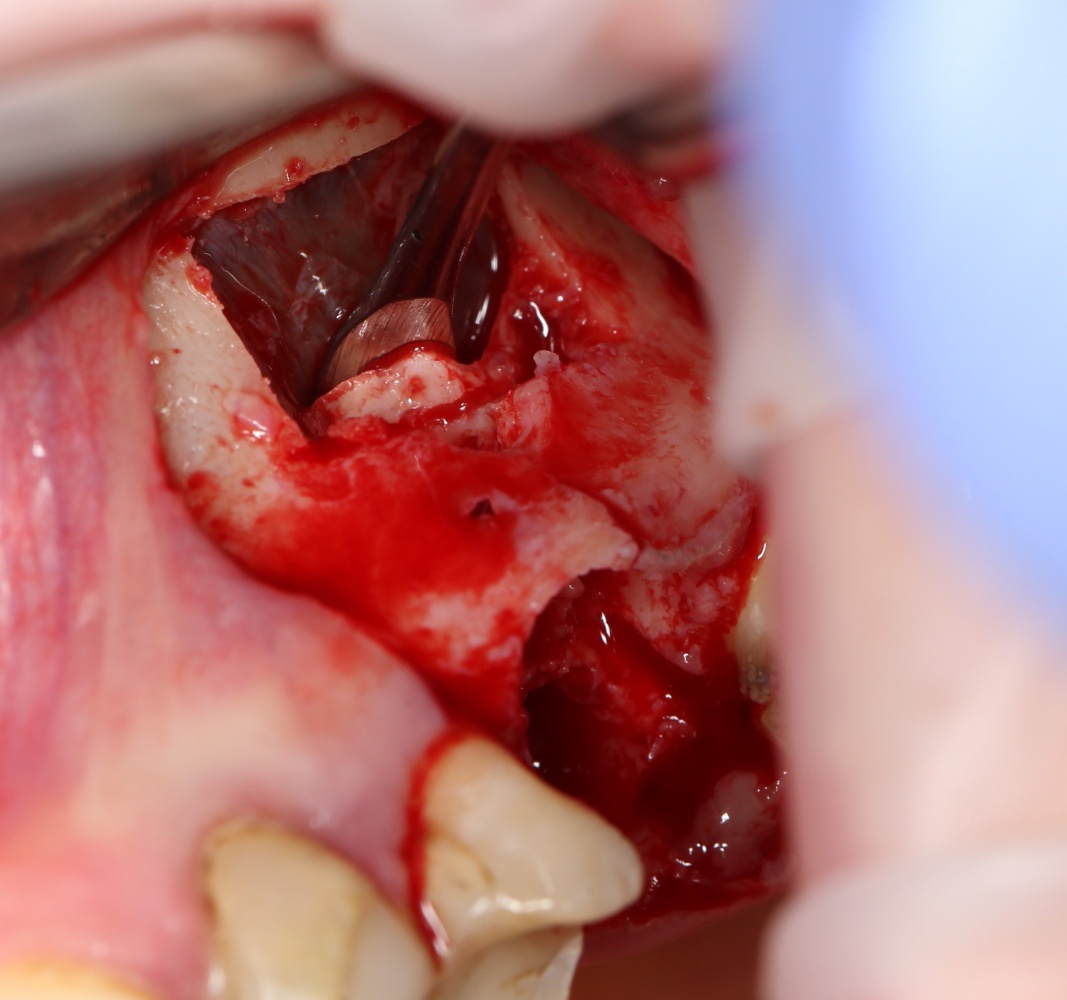

В ходе проведения операции синуслифтинга, у нас образовалась небольшая перфорация шнайдеровой мембраны:

Мы начинаем с того, что выводим ее в центр апертуры, попутно мобилизуем края. В результате, она несколько уменьшилась в размерах: